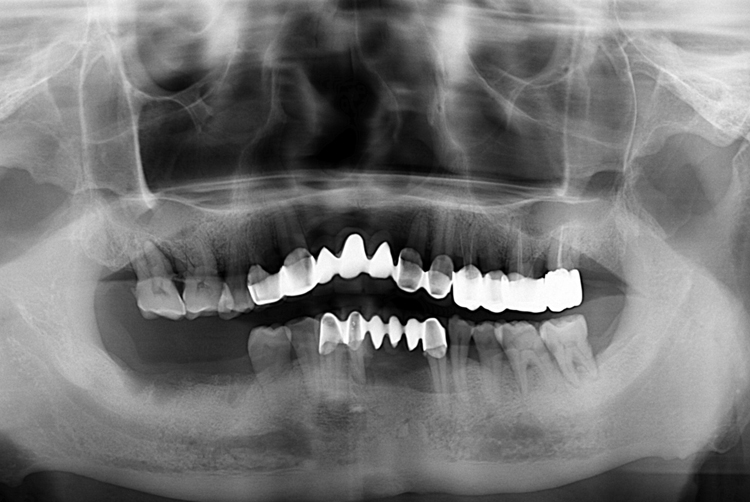

[임플란트] 어금니 임플란트

치료후 : 2016-12-16

세종치과는 많은 환자와 다양한 케이스를 바탕으로

항상 편안한 임플란트 수술을 제공하고자 노력하고,

오래동안 튼튼히 쓸 수 있는 임플란트 수술을 가장 큰 목표로 삼고 있습니다.